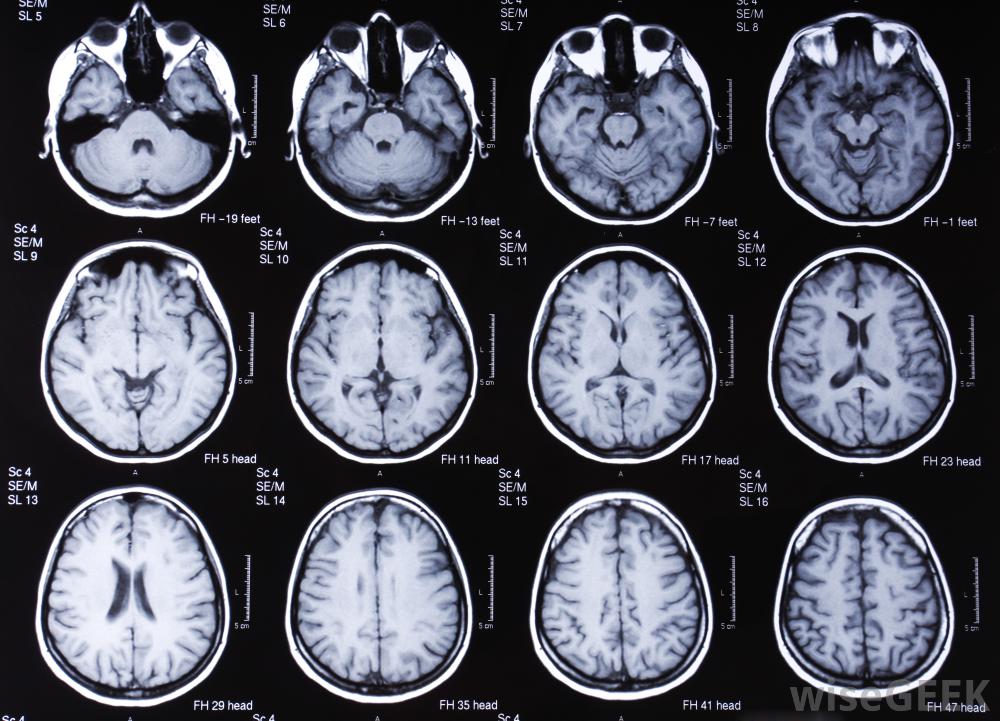

脑部的MRI扫描。T1核磁共振成像对大脑成像特别有用,因为灰质和白质的行为非常不同,而且清晰,清晰的大脑图像将被返回此外,脑部的高强度病变在核磁共振成像上会清晰地显示为非常暗的斑点,而像出血这样的东西则会根据其大小和强度而呈现苍白到白色。使用T1核磁共振成像可以让医生获得大脑内部的高分辨率图像,以收集用于制定治疗计划的信息对病人来说,人体内的各种组织都有不同的T1"重量,"指的是它们在核磁共振成像机中的活动。调整机器所用的脉冲,可以通过以不同的方式激发质子而返回各种结果。除了详细的黑白T1核磁共振图像外,这还可以用于创建三维核磁共振成像和彩色核磁共振成像这是医学诊断中最常见的MRI形式,可以使用或不使用造影剂。有时先在没有对比剂的情况下进行扫描,然后用对比剂重复扫描,以突出显示任何差异和结构异常。在T1 MRI中,患者需要安静地躺在核磁共振成像机的桌子上。机器会发出噪音,可能会让人感到不舒服,患者通常会被提供耳部保护,并可能会被给予镇静剂,以帮助他们在机器中保持冷静。在T1核磁共振成像期间移动会干扰读数,可能会迫使重复测试以收集准确的数据核磁共振成像机。